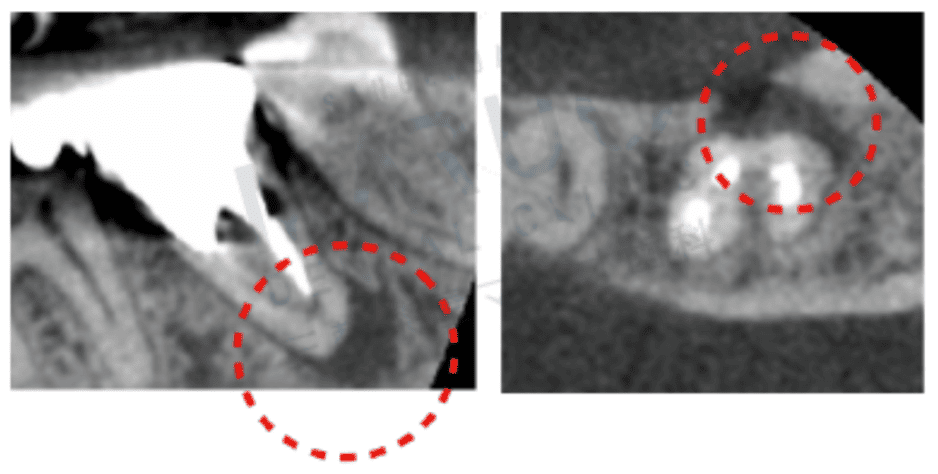

根管治療の成功率を高めるうえで、事前の正確な診断は欠かせません。従来の歯科治療では、平面的なレントゲン写真を頼りに根管の状態を推測していましたが、それだけでは根管の湾曲度合いや分岐部位、感染範囲などの把握が不十分な場合があります。

そこで当院では、CT撮影を活用した「三次元的な可視化」を取り入れ、患者さんの歯を立体的に解析するシステムを導入しています。CT画像を用いることで、従来の二次元画像では見落としがちな根管の分岐や歯根の破折ラインなども、より詳細に把握可能です。

下の画像は、デンタルレントゲンとCT画像の比較となります。丸を付けた部分が問題の箇所ですが、デンタルレントゲンだと、この丸の部分に黒い色がついていませんので、問題個所を見落としてしまう可能性があります。

治療計画を立案する段階でこれだけ正確な情報が得られれば、余分な歯質を削らずに済み、患者さんの歯をより保存しやすくなります。また、可視化されたデータを患者さんと共有することで、治療に対する理解を深めていただきやすくなり、不安や疑問を解消する助けにもなります。

治療中も高倍率ルーペを併用することで、根管の入り口や汚れが残りやすい場所をリアルタイムに視認しながら処置できるため、洗浄や消毒の精度も飛躍的に向上します。歯科医療の質を高めるだけでなく、患者さんの身体的・心理的負担を軽減し、再治療のリスクを抑制するためにも、先端の可視化技術の活用は重要です。